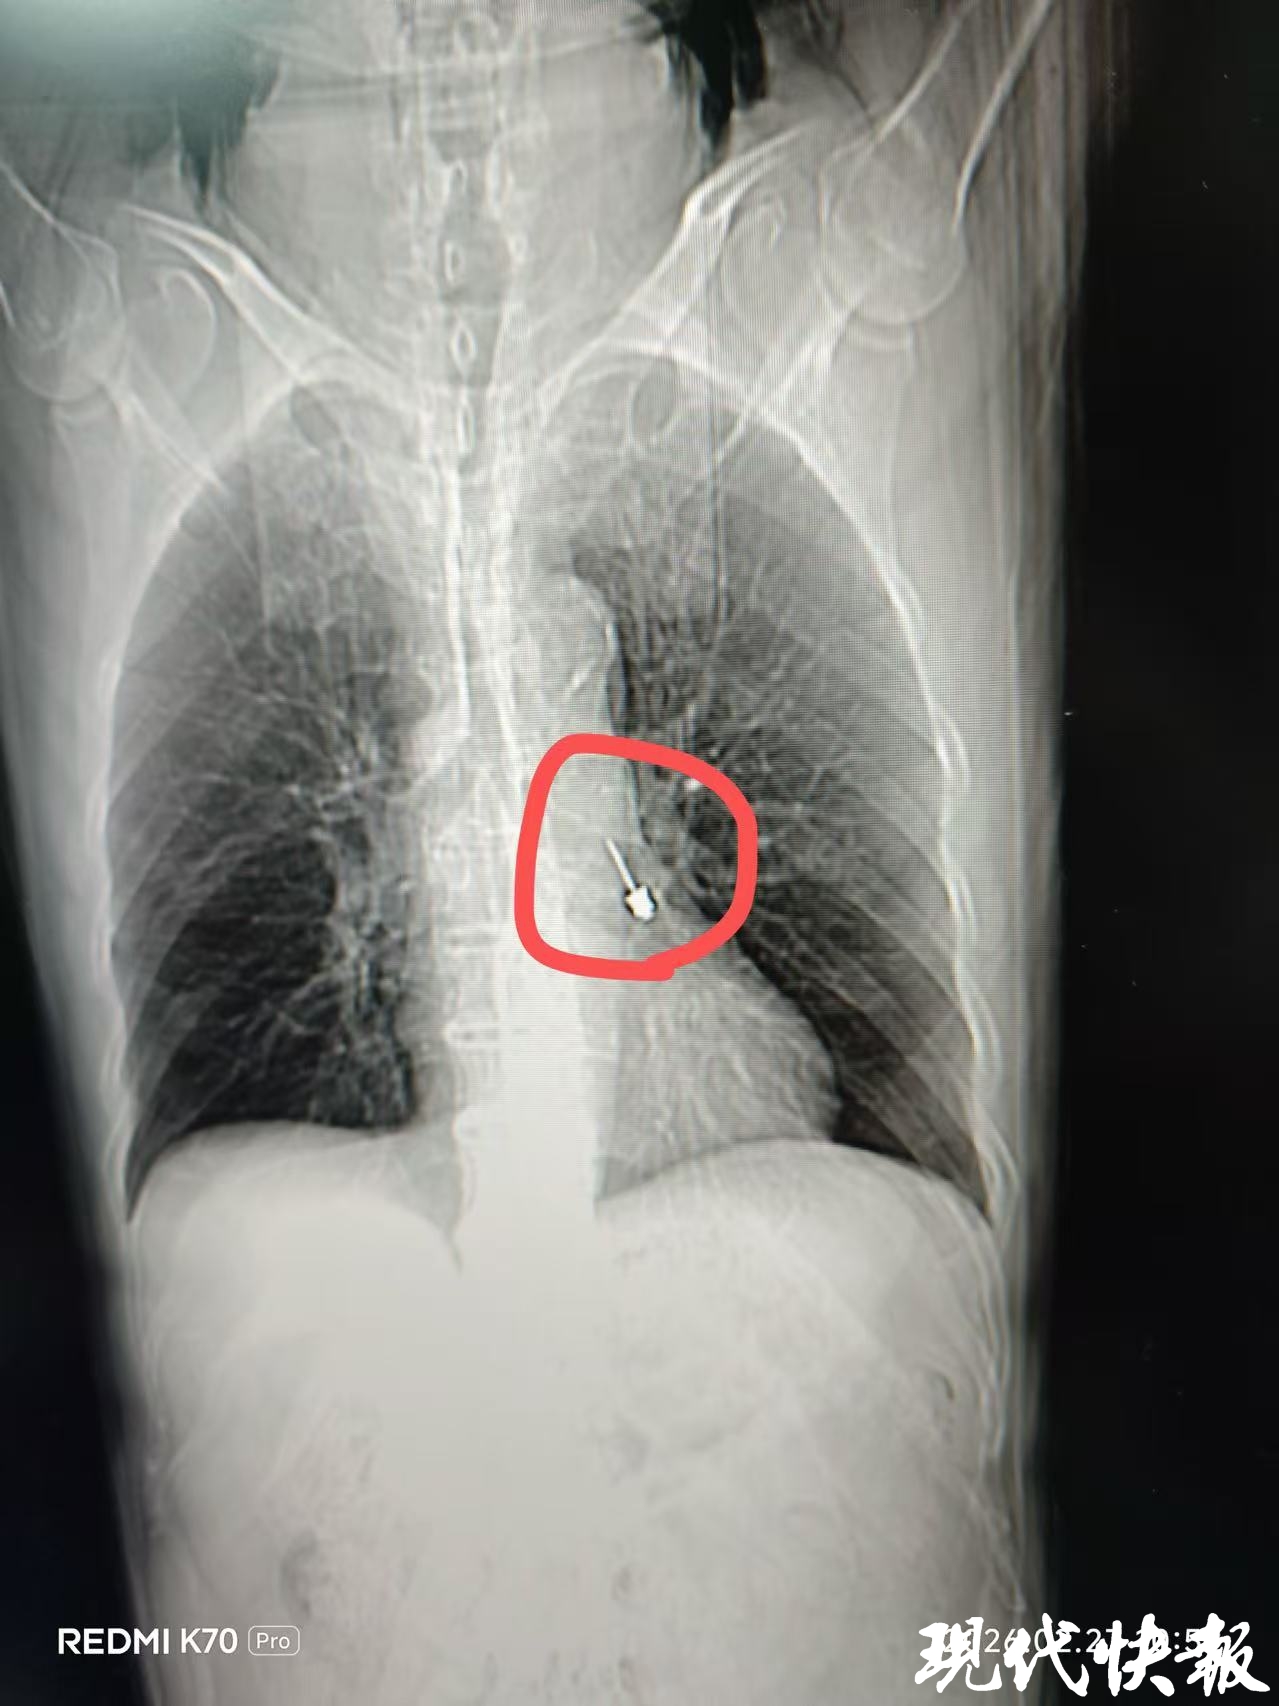

接诊医师查看李大爷的CT片后立即召集呼吸与危重症医学科会诊,会诊医师姜贺果副主任医师发现异物卡在左肺下叶近端支气管腔内,已经造成了中度气道梗阻,必须立即安排急诊手术。在科主任钱粉红的协调下,科室立即启动应急流程开展急诊手术。

当看到取出的异物,在场的医护人员既后怕又庆幸。这个异物“非同寻常”,是用于种植牙修复的螺丝刀。其头部尖锐,长度达2.5cm,万一刺破支气管壁引起出血或穿孔,后果将不堪设想。